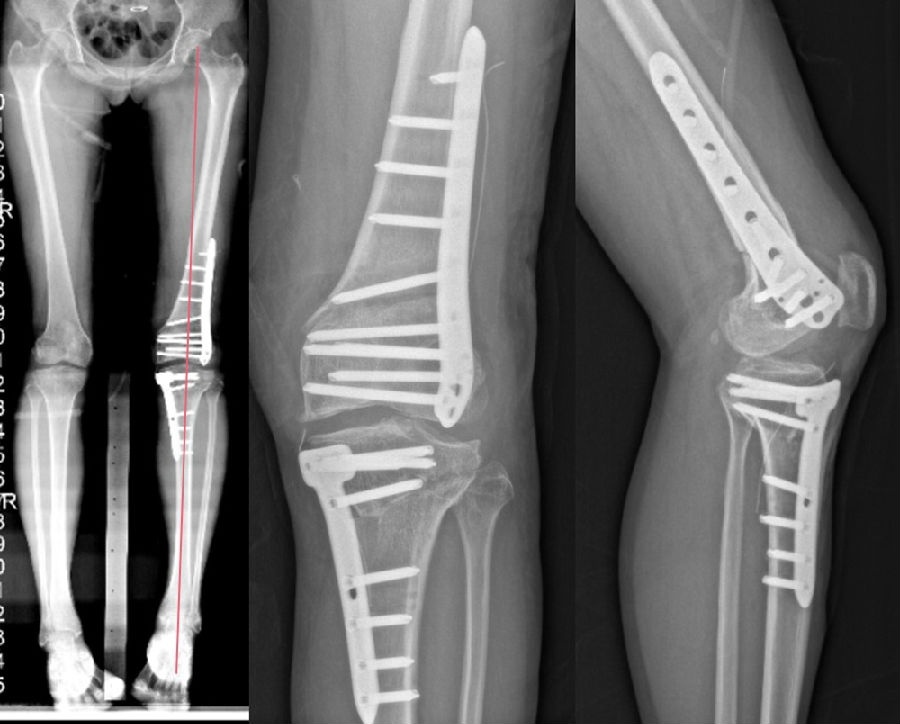

术前X线片

术前X线显示:

胫骨近端内侧角(MPTA):100°

股骨远端外侧角(LDFA):102°

关节线夹角(JLCA):

股骨远端后倾角(PDFA):85°

胫骨近端后倾角(PPTA):83°

术前计划:

股骨胫骨双截骨矫正下肢内翻畸形;

以关节线为参考,设定下肢目标力线;

避免单纯胫骨侧或股骨侧大角度矫正下肢畸形;

截骨后关节线不发生内倾倾斜,剪切力大;

拟行股骨外侧闭合楔+胫骨内侧闭合楔。

手术操作顺序:

股骨外侧闭合截骨11mm,恢复关节线方向(放平关节线LDFA88°)。

胫骨侧闭合13mm,矫正下肢力线至目标力线(居中)。

术后X线片

术后1个月

对于同时存在股骨和胫骨较大畸形的患者,建议同时行DFO+HTO双截骨,中短期临床疗效良好。可在恢复下肢机械轴线的同时纠正关节线的倾斜;还能避免单纯股骨侧或胫骨侧大角度矫正下肢畸形。